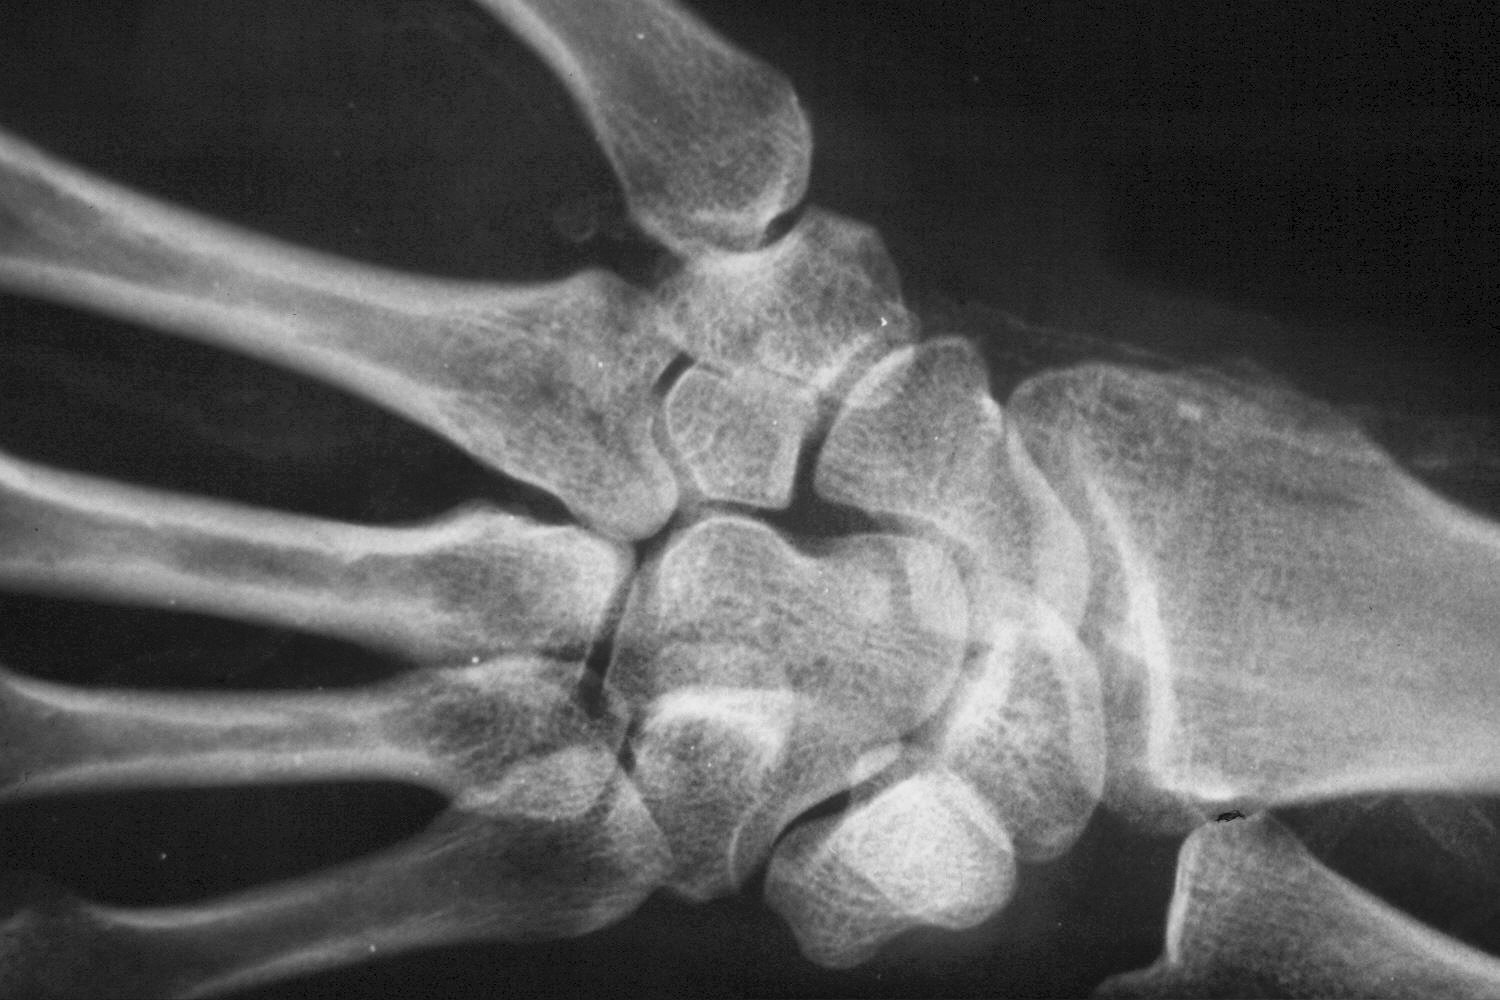

Appearance of the wrist and thumb after multiple debridements for progressive infected wound necrosis following failed radiocephalic shunt construction. The radial artery has been ligated.